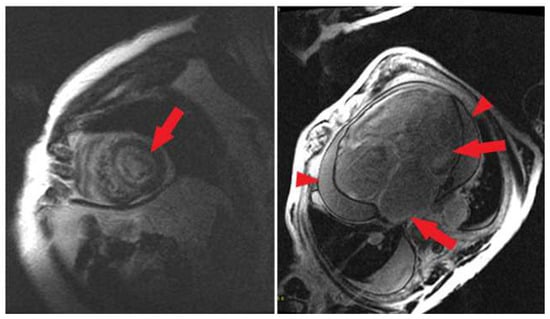

4.1. CMR Overview

4.2. Ventricular LGE

4.6. Ventricular Corridors and Scar Analysis